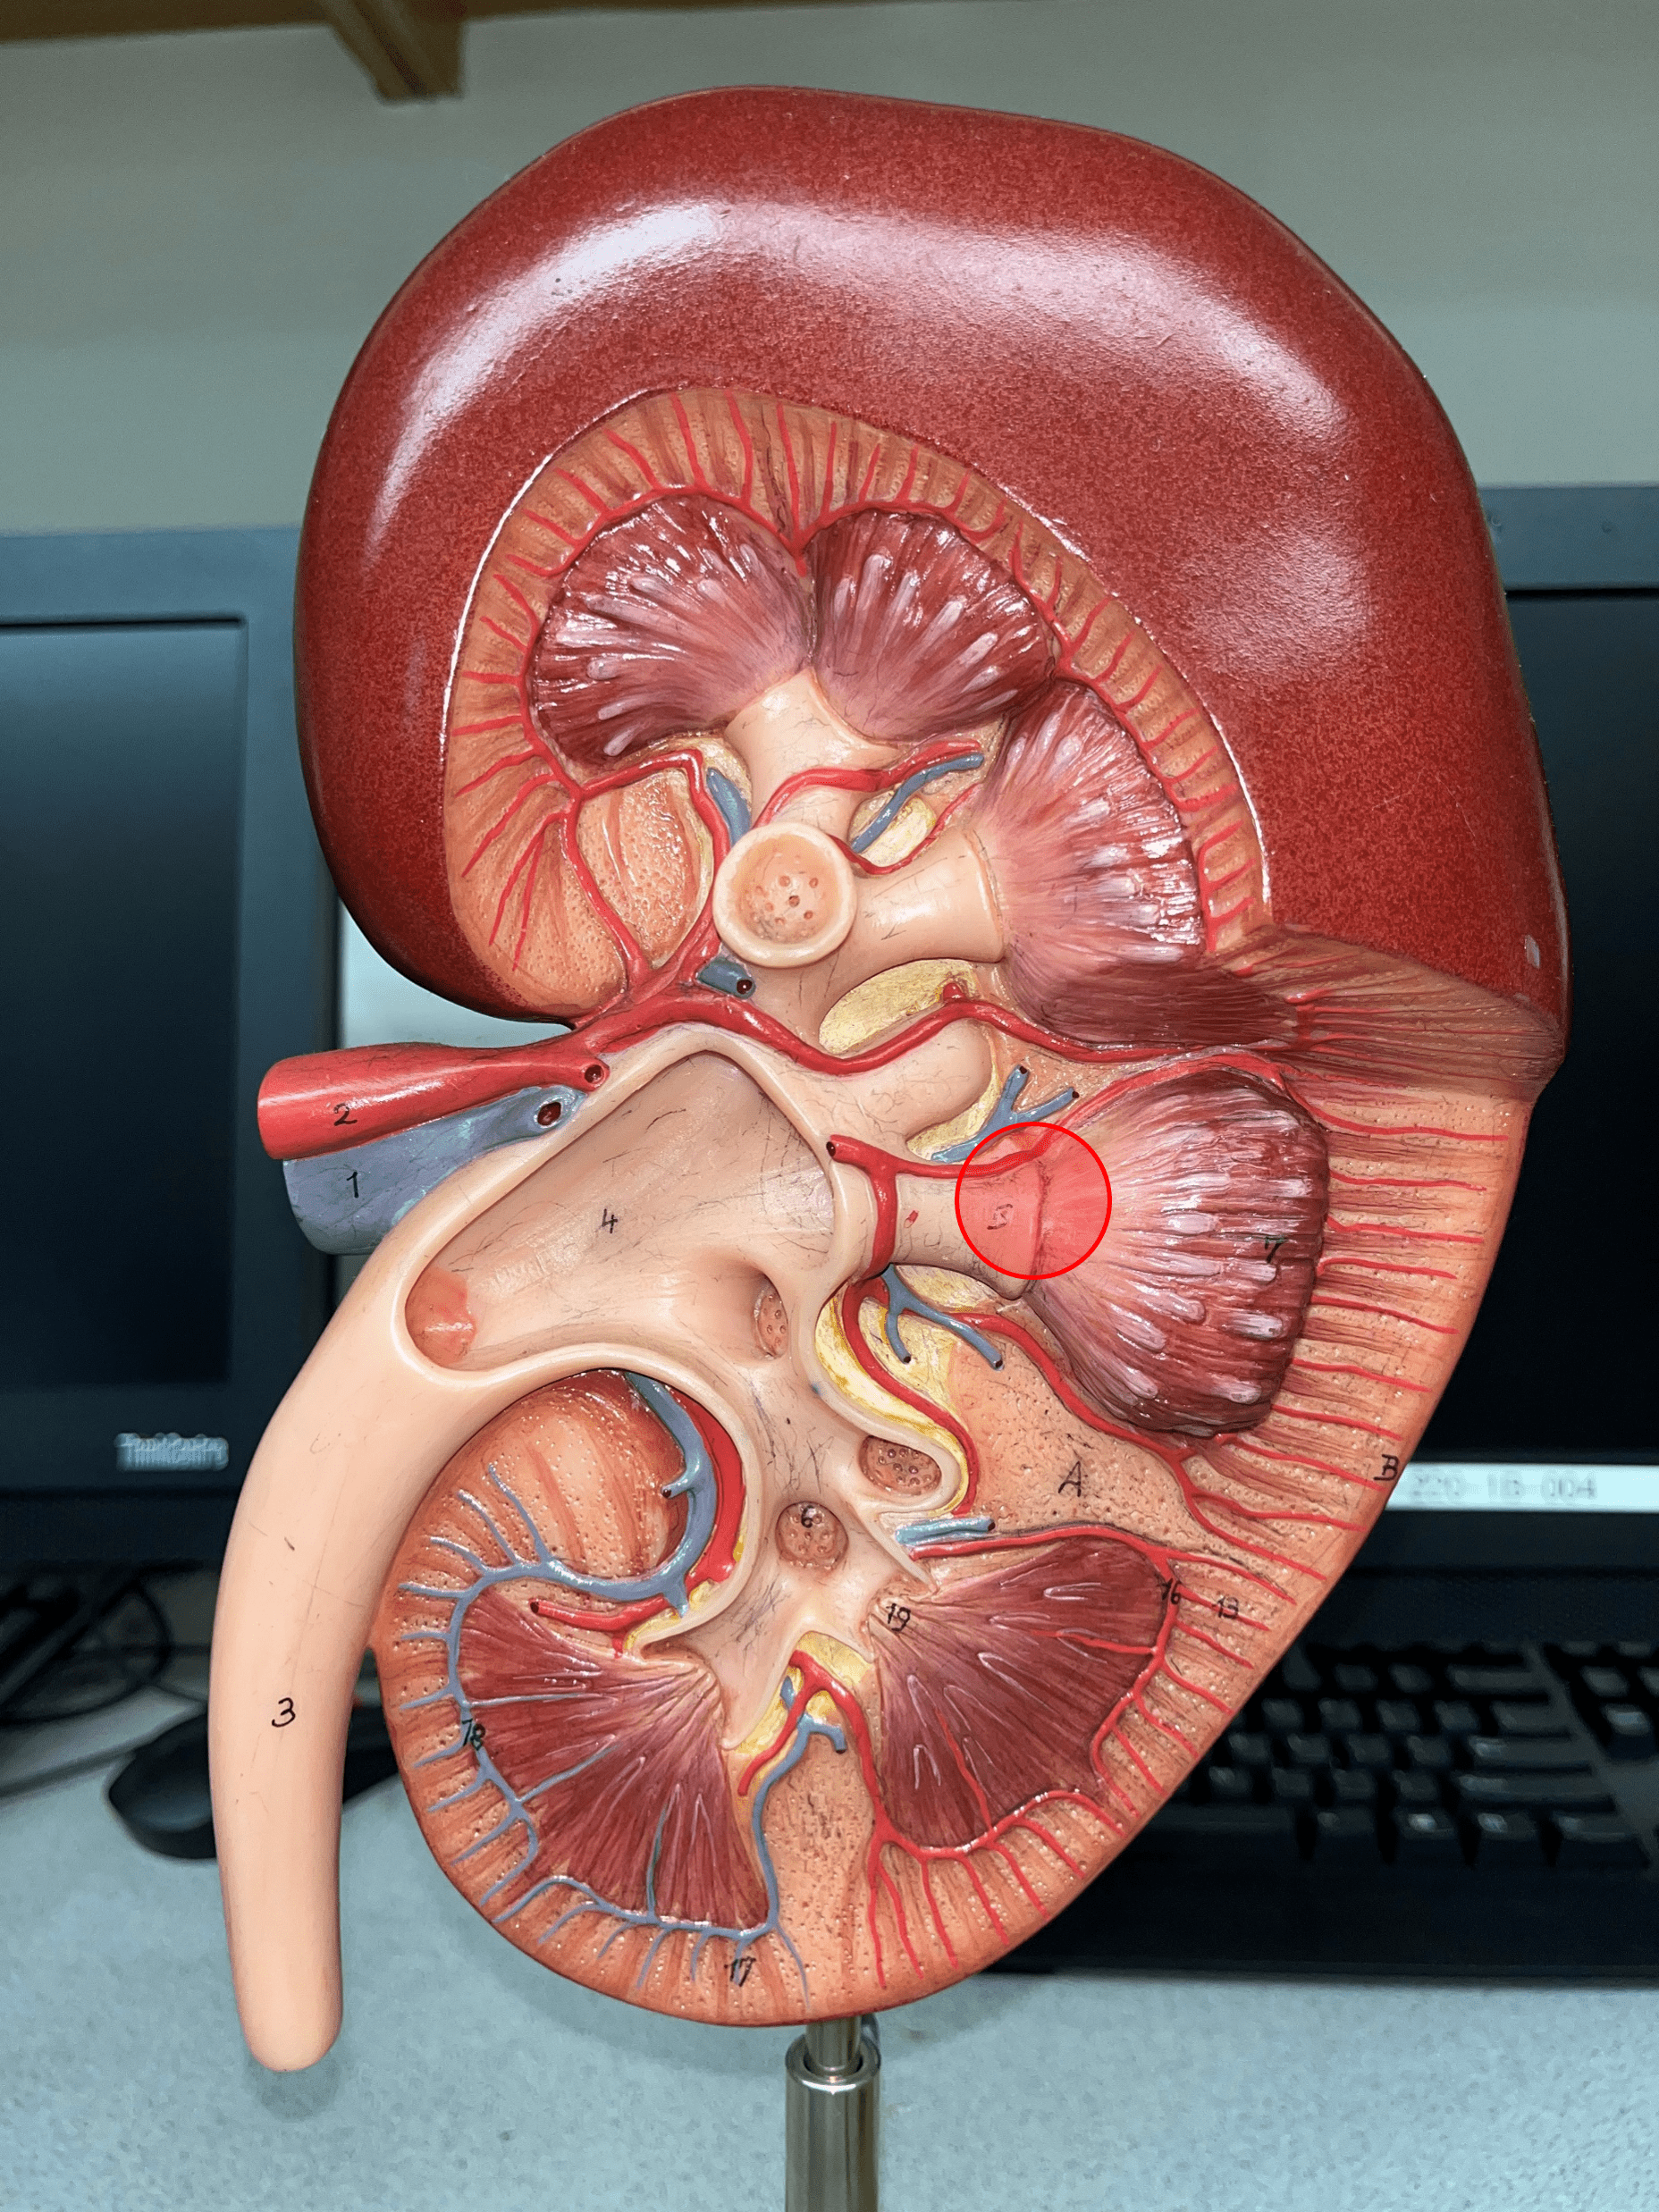

13

New cards

segmental artery

• Branches of the renal a.

• Branches into smaller interlobar aa.

• Branches into smaller interlobar aa.

14

interlobar artery

• Extends between the renal pyramids.

• Branches of a segmental a.

• Branches into smaller arcuate aa.

• Branches of a segmental a.

• Branches into smaller arcuate aa.